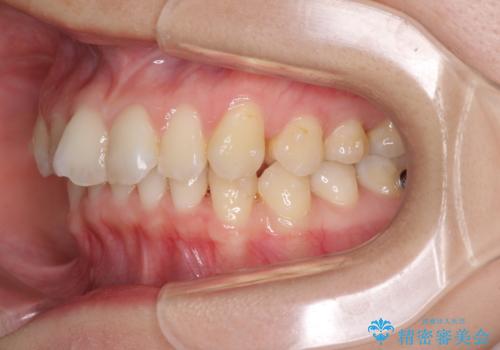

- 口元の深い咬み合わせ(ディープバイト)を気にして来院された患者様です。

インビザラインによる上下歯列の遠心移動(後方移動)により、口元のデコボコとディープバイトを改善することとしました。

下顎左右の犬歯とその後ろにある第一小臼歯、計4歯がシミュレーション通りに動かずディープバイトがなかなか改善されませんでした。

マウスピースの再製作を何度か行いましたがうまくいかないため、部分的にワイヤー矯正を併用することを提案しました。しかし、最も気になっていた前歯のデコボコはきれいに改善されたため、これ以上治療を希望されず、治療を終了することとしました。(今後気になった際には再開する予定です)